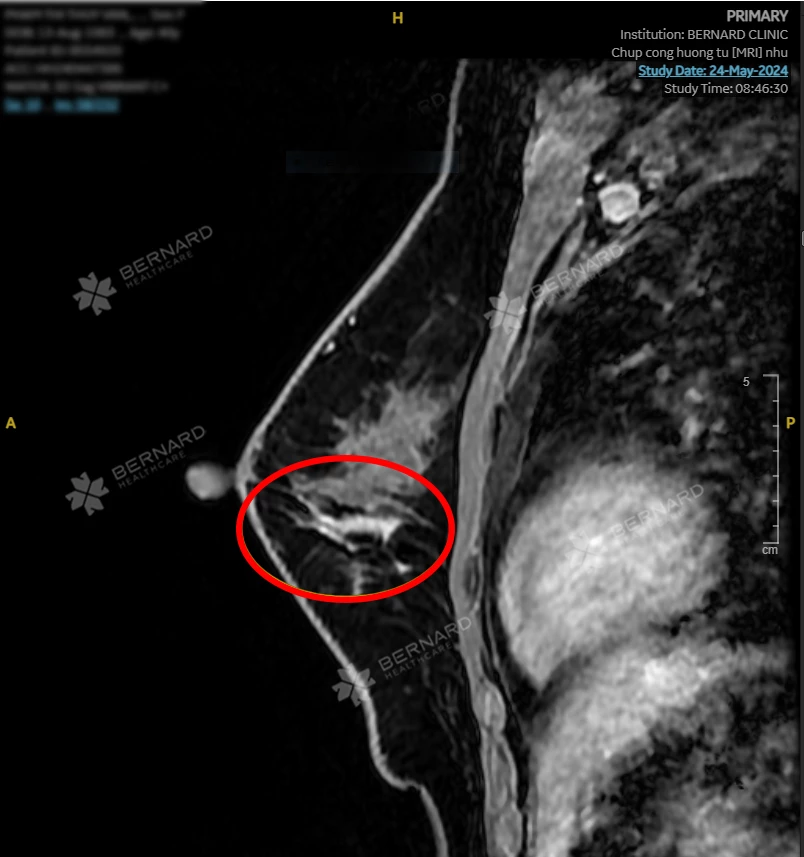

Kết quả hình ảnh MRI nhũ bất ngờ phát hiện tình trạng bất thường ở cả 2 tuyến vú. Cụ thể:

- Vú trái ghi nhận: Bất thường tín hiệu diện rộng chủ yếu 1/2 dưới ưu thế vị trí 6 - 8 giờ, giới hạn bờ kém rõ, tổn thương dạng đám, nốt, đường, không rõ hạn chế khuếch tán, phân loại tổn thương BI-RADS 4.

Nhận thấy bất thường trên MRI nhũ của bệnh nhân, ngay lập tức Hội đồng Y khoa Bernard chuyển gửi hội chẩn tham vấn ý kiến thứ 2 (second opinion) với các Giáo sư và Chuyên gia chẩn đoán hình ảnh Bệnh viện Đại học Yamanashi (Nhật Bản). Các bác sĩ Nhật đưa ra kết luận tương tự: Tổn thương trong ống tuyến, nghi ngờ UNG THƯ TẠI CHỖ (CARCINOMA IN SITU), phân loại BIRADS 4B.